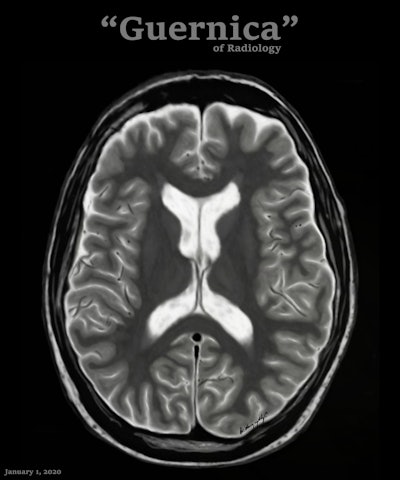

Art and radiology may seem like very different fields, but they can intersect in intriguing ways, particularly in medical imaging and the visualization of complex clinical data. Dr. Harun Yildiz has a keen interest in pediatric radiology, including ultrasound. All images provided by Dr. Harun Yildiz.

Dr. Harun Yildiz has a keen interest in pediatric radiology, including ultrasound. All images provided by Dr. Harun Yildiz.

Dr. Harun Yildiz, a radiologist at Dortcelik Children's Hospital, Bursa, Turkey, is convinced that beauty exists within medical images, and appreciating the aesthetic qualities can boost mental health and help avoid burnout. Ahead of his first lecture about radiological illustrations on 20 November 2025 at 8 p.m. Turkish time/6 p.m. CEST, we asked him to elaborate on his passion for art.

Conceptually, I think it is possible to define the term “radiological illustration” as an emerging discipline that transforms medical imaging data into an aesthetic and didactic narrative. I emphasize that with the motto “pixel by pixel handmade.” I am trying to open a “new path” for the use of visual communication in medical education by trying to combine scientific accuracy in radiological terms with artistic creativity. With this statement, I am trying to express that instead of modifying radiological images, I draw each pixel by hand using technological tools and create a new visual that is both artistically and scientifically original, while remaining faithful to radiological principles.

It’s important to note that radiological illustration should not be confused with medical illustration. The former has yet to be systematically defined in the literature. I believe it deserves recognition as a distinct sub-branch within the broader medical illustration domain.